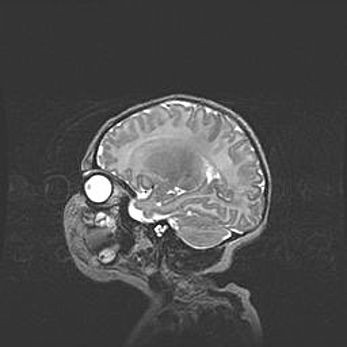

Наружная гидроцефалия с возможной атрофией височных областей.

Возраст: 28 дней

Вес: 3670 г

Пол: мужской

Окружность головы: 38 см

Срок гестации: 40 недель

Гидроцефалия головного мозга у новорожденных – это заболевание, которое характеризуется скоплением избыточного количества спинномозговой жидкости в желудочковой системе головного мозга в результате затруднения её перемещения от места выработки к месту поглощения в кровеносную систему или вследствие нарушения абсорбции. При открытой наружной форме гидроцефалии у новорожденных расширяются и переполняются субарахноидные пространства.

При нормотензивных  формах,  которые,  как  правило,  являются  следствием  перенесенных ишемических  повреждений  паренхимы  мозга,  возможно  сочетание микроцефалии  с нормотензивной гидроцефалией. В основе данных изменений лежит атрофия больших полушарий с преимущественной  локализацией  в  лобно-височных  областях.